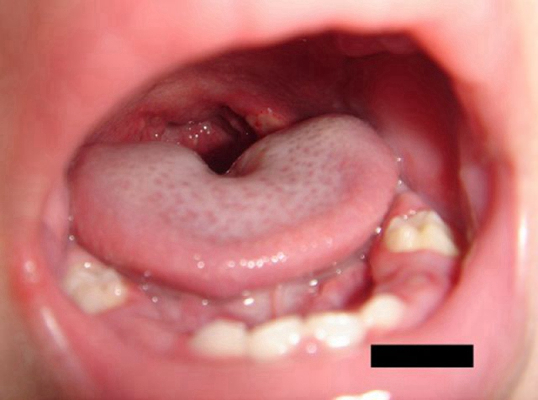

A:舌癌一般是在舌側緣出現腫物,有外生型、潰瘍型和浸潤型。最常見的是外生型和潰瘍型,一般在早期就是在舌側緣出現一個深的潰瘍,而且潰瘍長期不愈。和普通的口腔潰瘍不同,舌癌的潰瘍兩個月以上也不會自行癒合,創面不斷的增大、加深,加深到一定程度舌頭會出……

A:舌癌是口腔頜面部常見的一種惡性腫瘤,多數為鱗狀細胞癌,多見於舌緣,常為潰瘍型或浸潤型,增長快,疼痛明顯,浸潤性強,可導致舌運動受限,進食及吞嚥困難,男性多於女性。舌癌的病因目前尚不明確,多數認為與環境因素有關,另外,神經因素,內分泌因素,機……